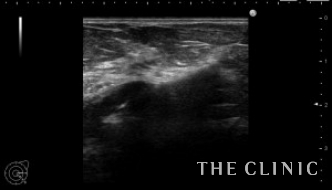

このしこりがカプセル内を移動するので、エコーのプローブで移動しないように圧迫固定して穿刺吸引しました。

吸引した壊死脂肪です。